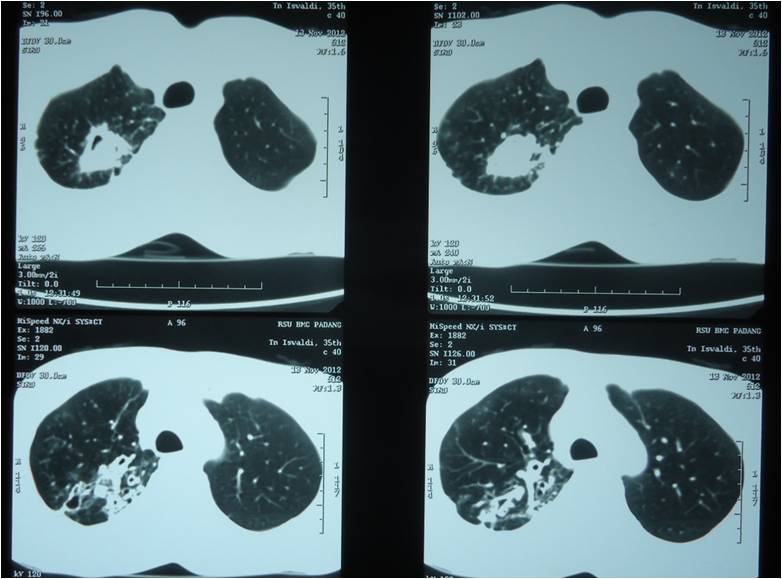

From radiographic there is collapse lung, it was shown collapse line on the right hemithorax, and fibroinfiltrat with multiple cavities on both hemithorax.

Dx. : Bronkopneumoni dengan bronkiektasis dextra dan efusi pleura sinistra. : Ca rectosigmoid tipe annulair. A mild chronic inflammatory infiltrate may be present. Guaifenesin for fibro is a popular treatment protocol with a great number of anecdotal claims that it can relieve fibromyalgia symptoms.